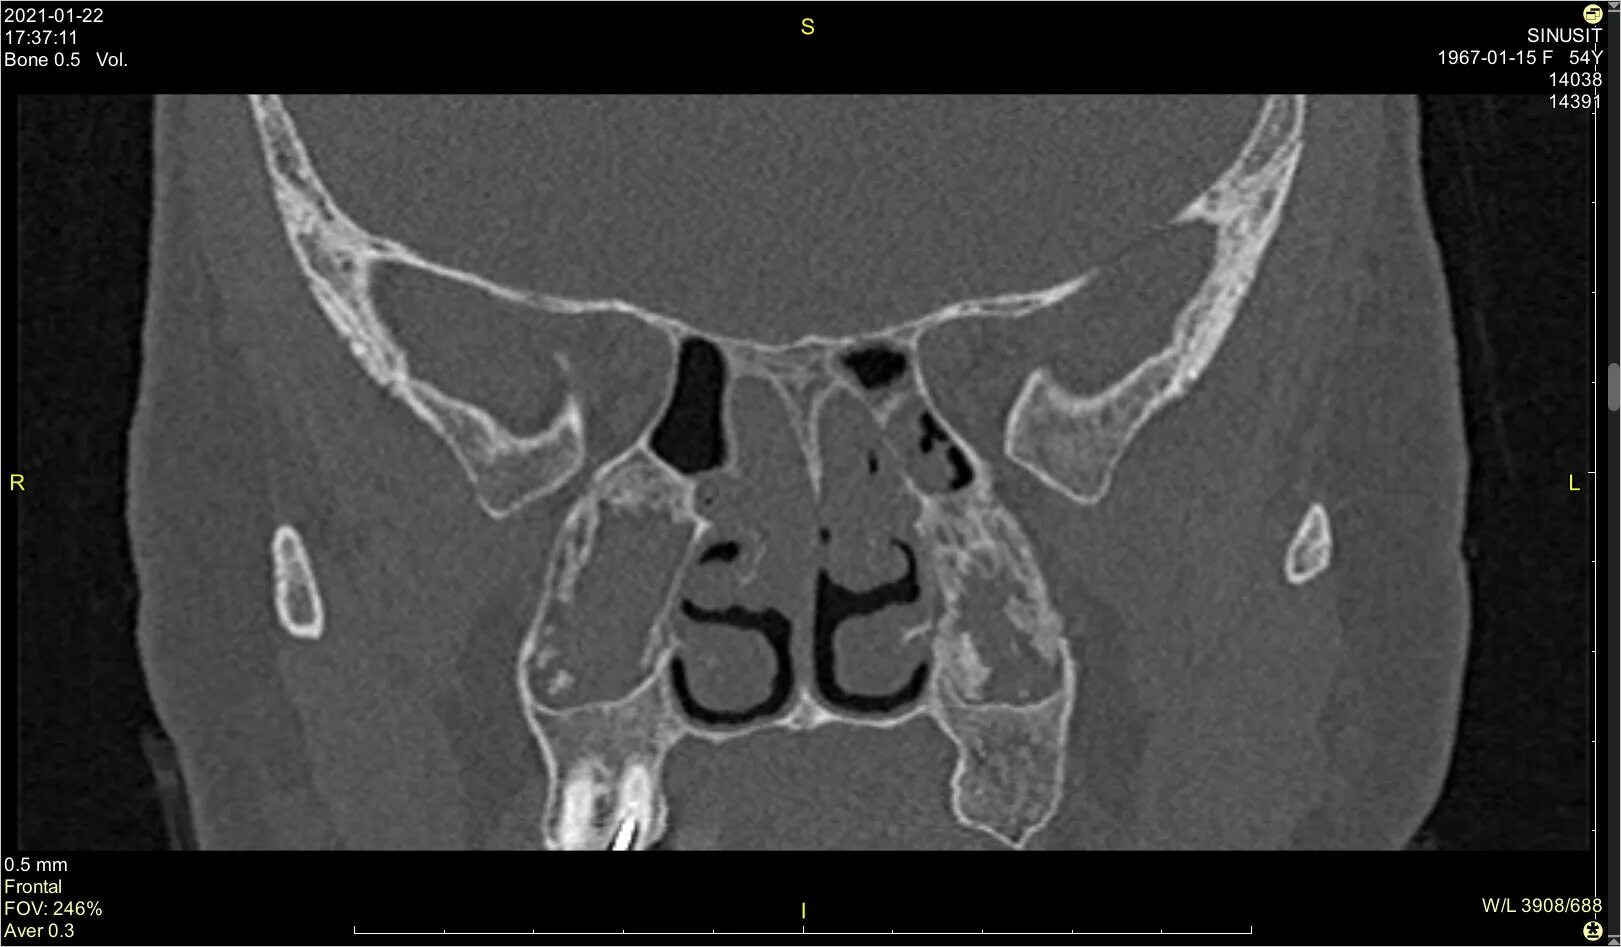

Синусит на кт